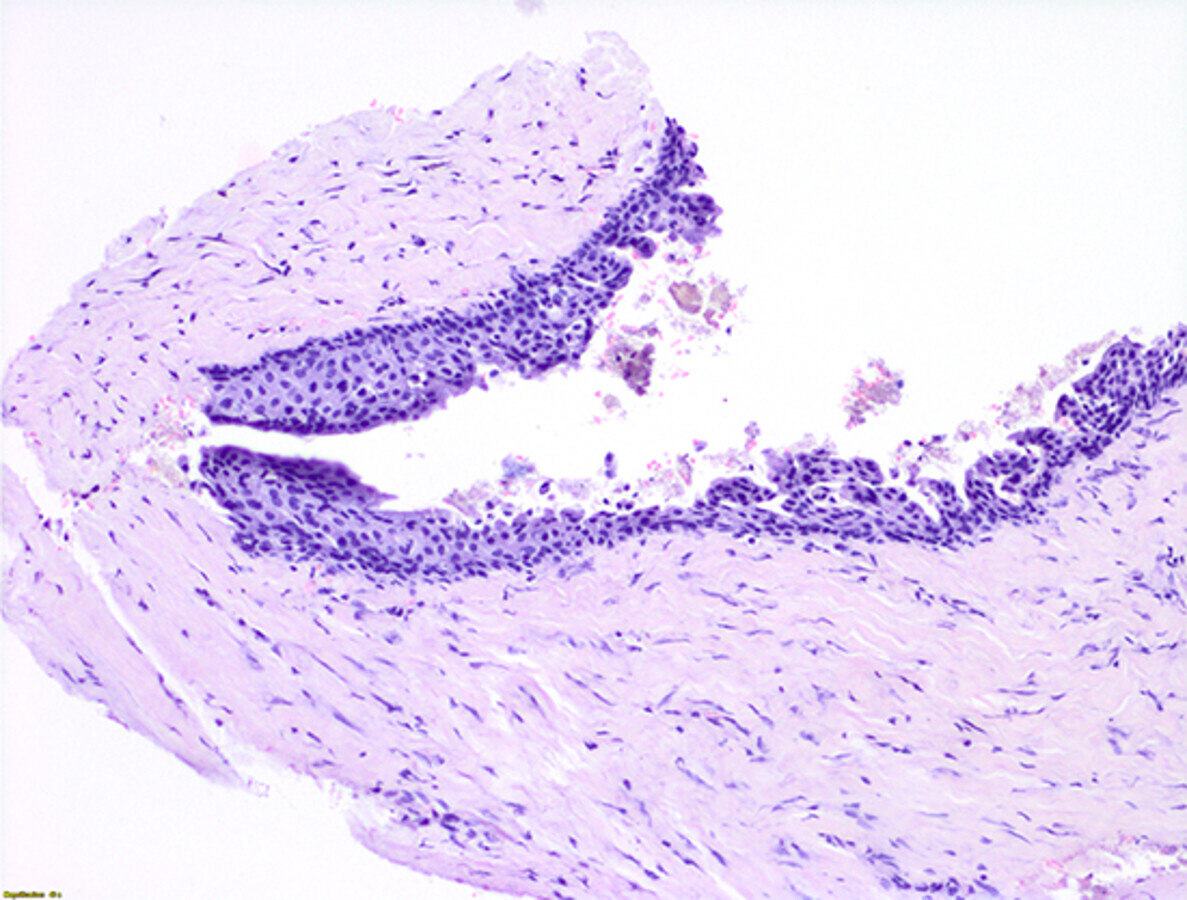

Los fragmentos analizados estaban constituidos por una pared conectiva fibrocelular densa, que mostraba un infiltrado inflamatorio difuso, así como focos con reacción a cuerpo extraño con cristales de colesterol, células gigantes multinucleadas y alguna espícula ósea. Se reconoció un epitelio de revestimiento delgado, poliestratificado no queratinizado, parcialmente desprendido en algunas zonas (Fig. 9). Estos hallazgos confirmaron el diagnóstico presuntivo de quiste odontógeno del desarrollo (quiste dentígero). La histopatología fue realizada por el Dr. José Manuel Aguirre Urizar (Servicio Diagnóstico Patología Oral y Maxilofacial, Las Arenas - Areeta, Bizkaia, España).

Figura 9. Análisis histopatológico. Se observa la pared quística compuesta por tejido fibroso y tejido conectivo revestido por un epitelio estratificado no queratinizado, y algunos fragmentos óseos.